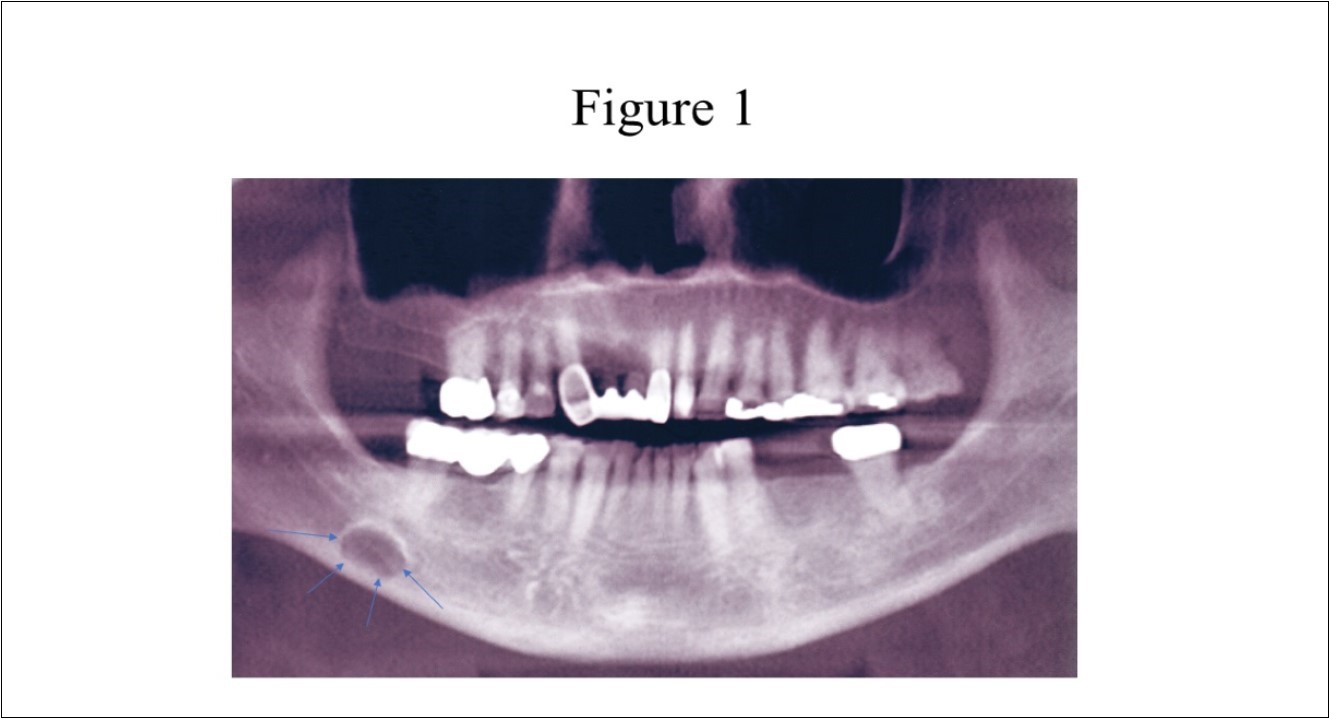

Radiographic features (Figure 1) of the SBC are a well-circumscribed unilocular, round or elliptical shaped radiolucency in the posterior mandible that are approximately 10 to 30mm in length. 1,3,4The radiographic lesion is often incidentally discovered when the patient completes a routine panoramic radiograph at the dentist office and does create concern for the dentist as it can mimic a cystic lesion.3,5,6

Figure 1.Panoramic radiograph of classically described SBC of the right posterior mandible illustrates the well-defined unilocular radiolucency in the right posterior mandible between the inferior alveolar canal and the inferior border of the mandible (arrows).